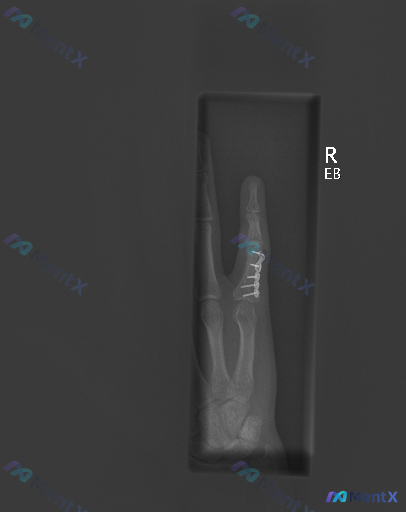

整理到一份右示指近节指骨骨折术后的X光随访资料,先不说临床背景,只看影像描述,大家第一感觉怎么样? 影像核心发现: - 右手示指近节指骨可见金属钢板及螺钉固定,位置良好 - 钢板覆盖区域因金属伪影遮挡,原始骨折线愈合情况难以清晰评估 - 未遮挡区域骨皮质连续性尚可,关节间隙正常,未见明显骨质破坏或脱...